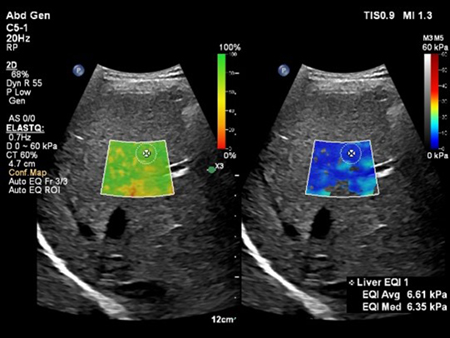

2. Auto ElastQ(オート・エラストキュー)

Shear Wave Elastographyを用いて肝臓の硬さを非侵襲的に計測するアプリケーションElastQ(エラストキュー)に,自動化機能が追加された。Auto ElastQは,計測に適したフレームやROIポジションを自動で判別し,計測結果を表示することが可能。これにより,これまで課題であった検査時間を最大60%短縮し[2],99%の再現性が報告されている。[3]

Auto ElastQによる肝硬度の自動計測:適切なフレームとROIポジションが自動で判別され計測が行われる